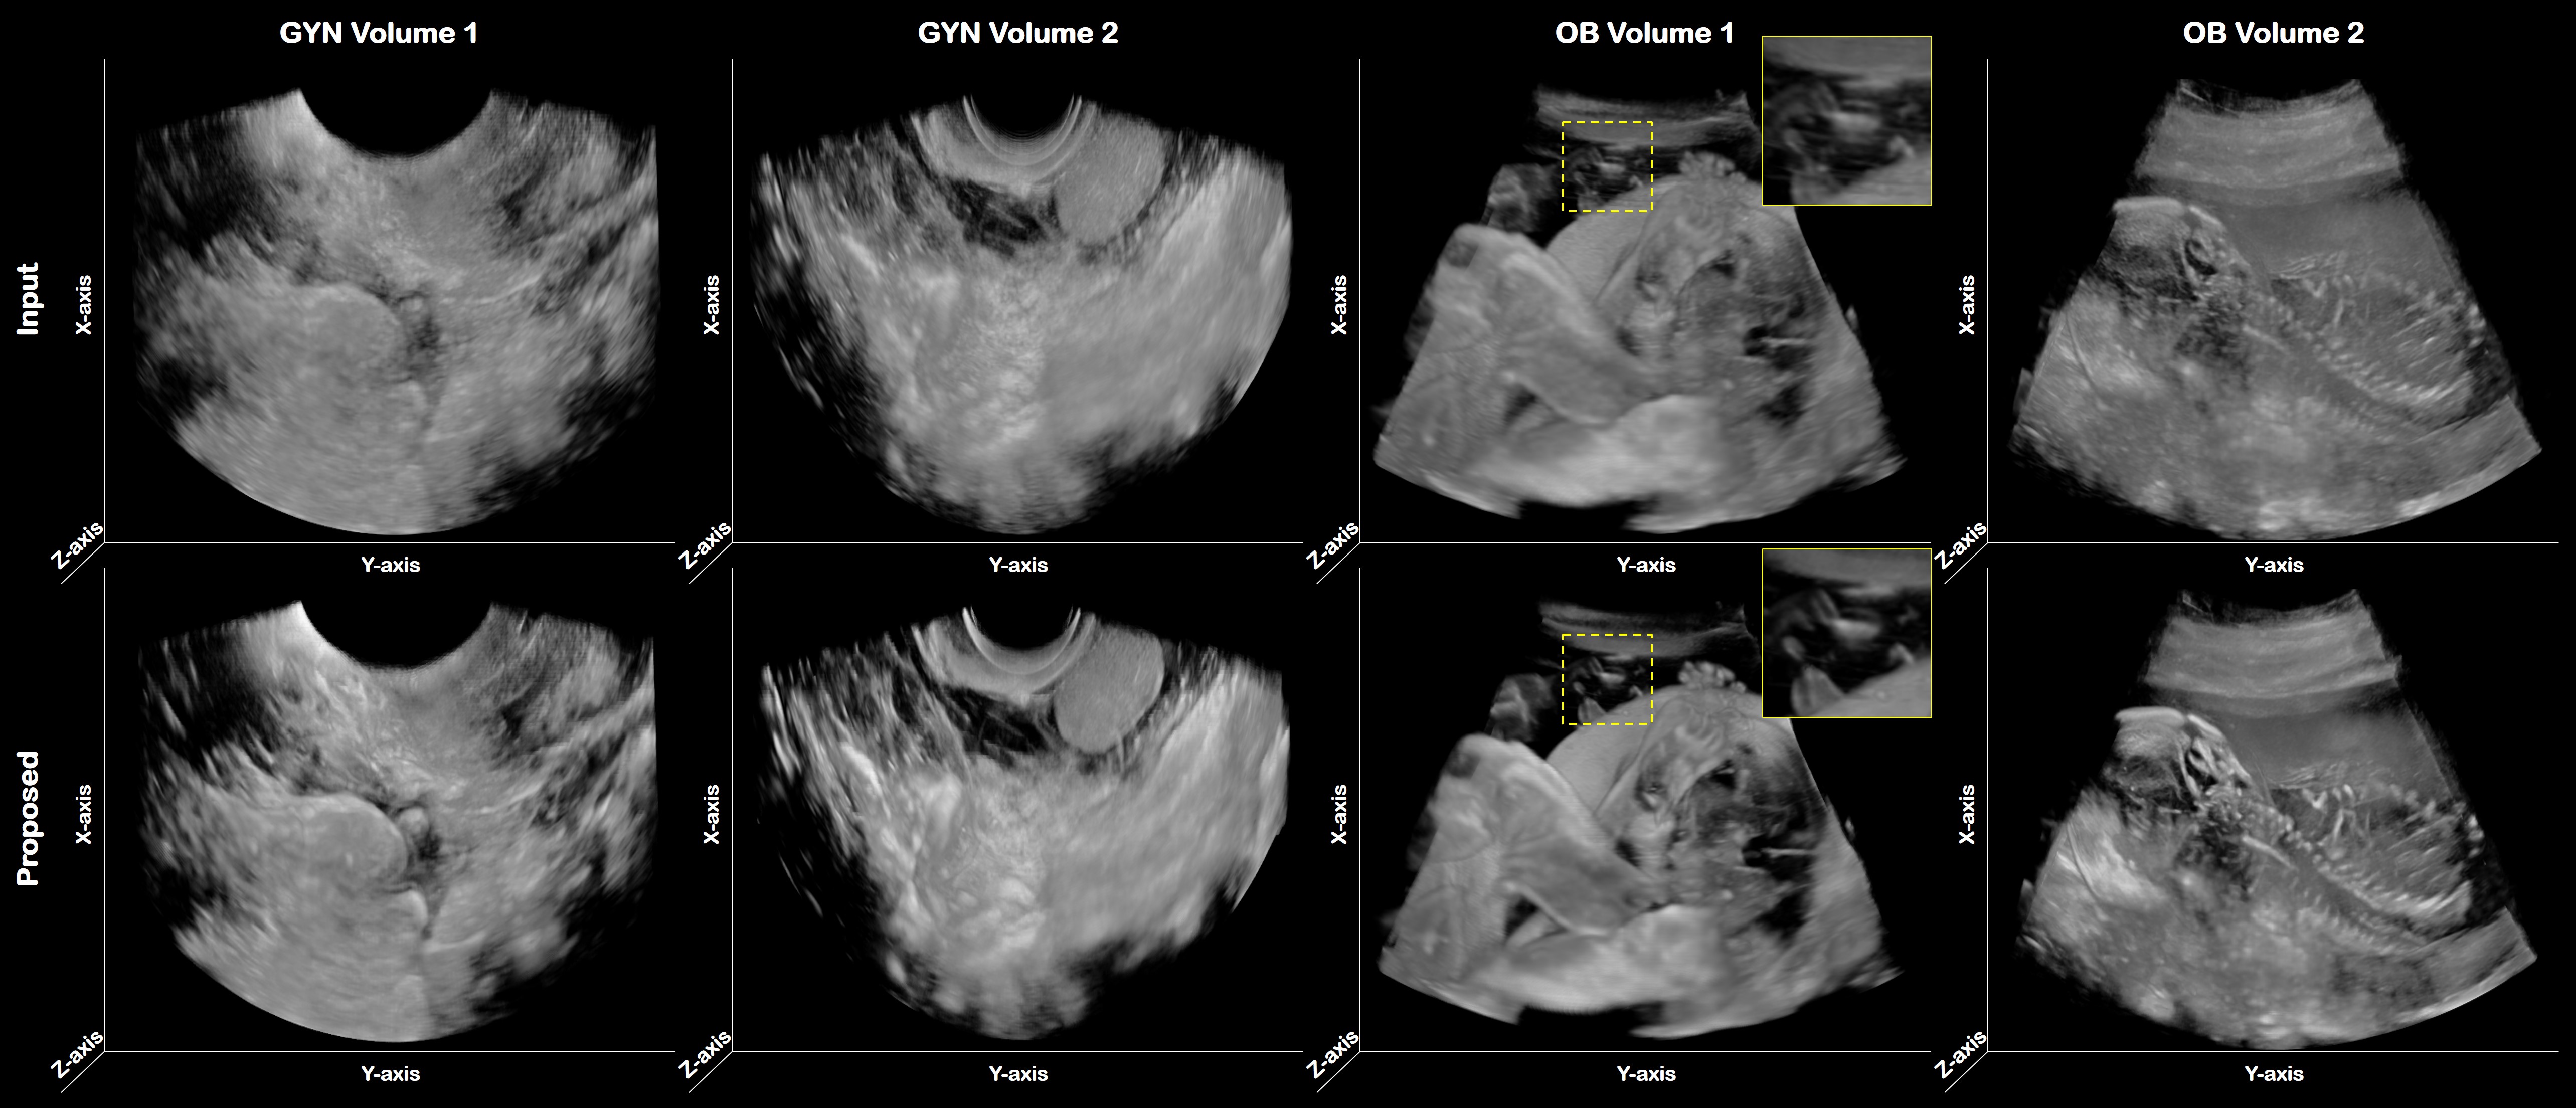

5.3 3-D Volume Rendering

In order to verify the effect of the proposed method in the 3-D volume image, we generated a 3-D rendering view with the system Paraview 5.10.0. In Fig.  10, we have shown two GYN and OB volume data sets. The first row is an input image and the second row is output by the proposed method. We have all generated A-plane images that are cut along the elevation axis and fed into the trained network. Then the output planes are concatenated along the elevation axis to acquire original volume data. All inputs and proposed paired volume images were visualized using the same intensity scale.

As shown in Fig. 10, the structure boundaries are clearer in the proposed volume than in the input volume. In particular, the side-lobe artifact has been suppressed and its structure is then better visible. While artifacts are shown in input volume images which is highlighted as a yellow box at the top of the image, the proposed method suppresses well. The arm and head of the fetus are more clearly visible compared to the input volume image. In the fourth column in particular, the spine of the fetus can hardly be found on the input volume image, but it is easy to identify with the proposed method.

Refer to caption

Fig. 10: 3-D volume rendering results. The first and second row denote the input and the results from the proposed method, respectively. The first and second column are two different test gynecology volume sets, and the third and fourth column are obstetric volume test sets.